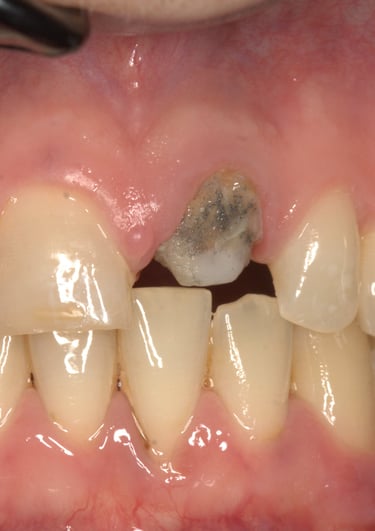

Un paziente si è presentato alla nostra attenzione con un problema di decementazione ripetuta della corona su un incisivo centrale superiore (dente 21). Oltre all'evidente instabilità protesica, la corona mostrava una discrepanza estetica marcata rispetto ai denti naturali adiacenti, compromettendo l'armonia del sorriso.

Dopo un'approfondita analisi clinica e radiografica, sono stati individuati i seguenti problemi:

Corona incongrua: non solo non si armonizzava con i denti circostanti, ma risultava anche inadeguata dal punto di vista funzionale.

Trattamento endodontico inadeguato: il precedente trattamento canalare era insufficiente, lasciando il dente vulnerabile a infezioni e compromettendone la prognosi a lungo termine.

Perno moncone inadeguato: la mancanza di stabilità del perno esistente causava la continua decementazione della corona, rendendo necessario un intervento risolutivo.

Corona Incongrua

Condizioni Iniziali

Moncone non ritentivo

Trattamento Canalare Incongruo